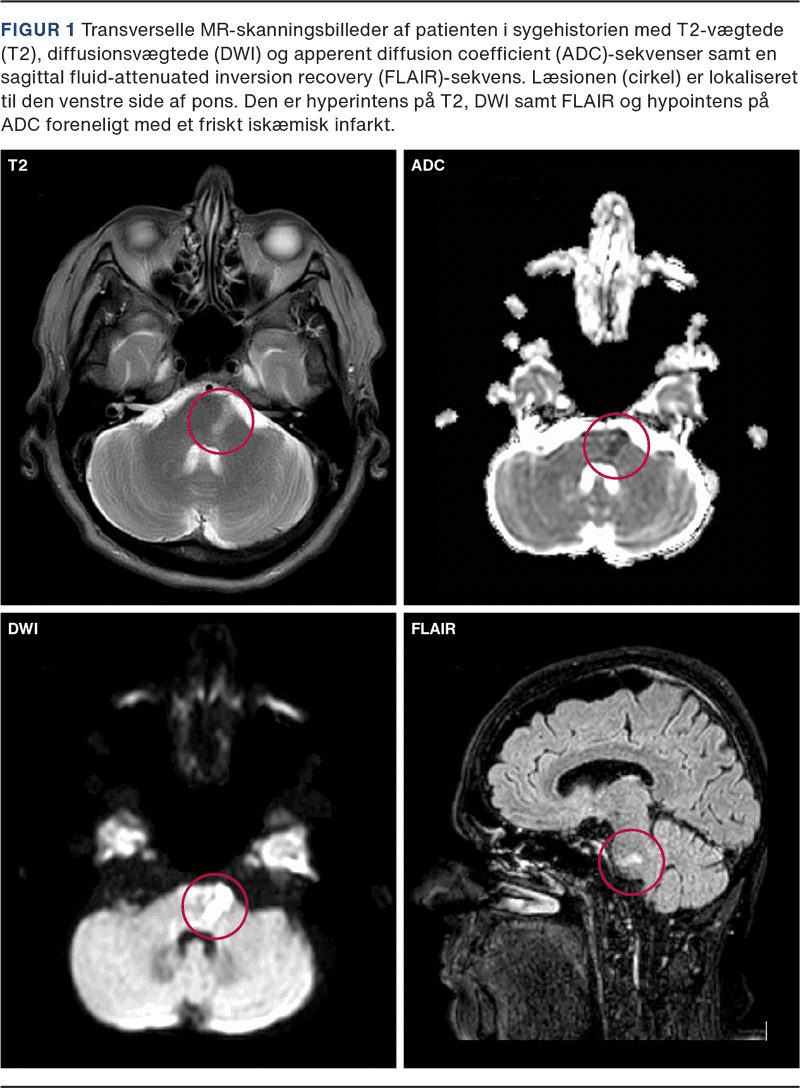

MR-skanning af cerebrum to dage efter debut viste et friskt venstresidigt pontint infarkt (Figur 1) foreneligt med patientens symptomer. UL-skanning af halskar viste forkalkninger bilateralt uden stenoser. Blodprøvescreening, ekg, telemetri, urinstiks og SARS-CoV-2-podning ved indlæggelse var upåfaldende. CT-angiografi blev ikke udført, da patienten hverken havde nakkesmerter, hovedpine, Horners syndrom eller fluktuerende symptomer.